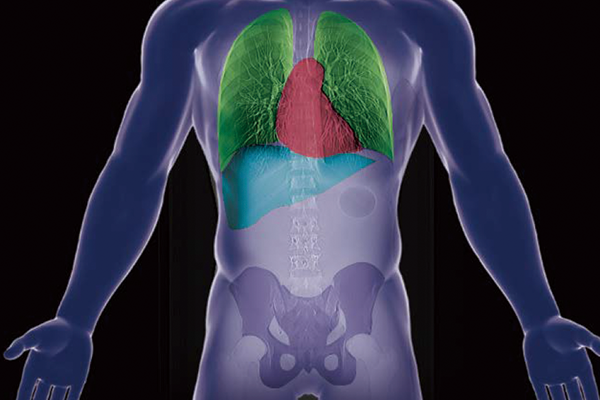

The captured scanogram image can be used to automatically set the scan range. This can be expected to be shorten the setting time. By using Fujifilm's automatic organ segmentation technology*7, which was developed utilizing deep learning, it contributes to the scan of a total of 14 types, including the head and chest. In addition, since the margin of the scan area can be set in advance, the scan area can be customized according to the operation of each facility. The operator can also check and adjust the automatically calculated scan area.

REiLI makes it happen to extract organs and simplify your work.

Lung lobe

Liver

Kidney

Colon